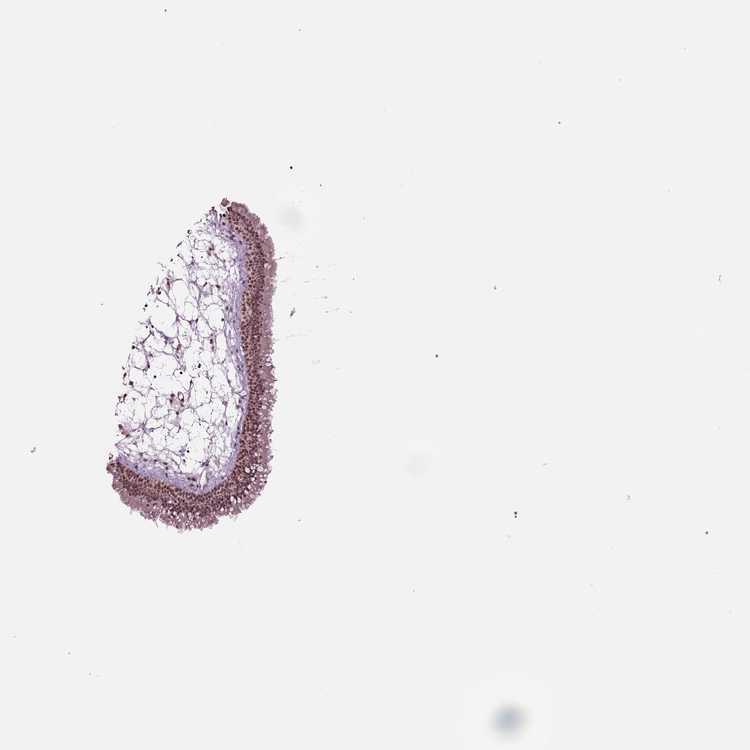

TISSUE PRIMARY DATA NASOPHARYNX Show tissue menu

NASOPHARYNX - Antibody stainingi

Antibody staining in the annotated cell types in the current human tissue is reported as not detected, low, medium, or high, based on conventional immunohistochemistry profiling in selected tissues. This score is based on the combination of the staining intensity and fraction of stained cells.

Each image is clickable and will lead to virtual microscopy that enables deeper exploration of all samples and also displays staining intensity scores, fraction scores and subcellular localization as well as patient and tissue information for each sample.

Antibody HPA076960

Basal cells Medium

Ciliated cells (cell body) Medium

Ciliated cells (cilia axoneme) Not detected

Ciliated cells (ciliary rootlets) Not detected

Ciliated cells (tip of cilia) Not detected

Goblet cells Not detected